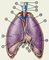

Легкие (рис. 1) по форме напоминают половины вертикально рассеченного конуса; они покрыты серозной оболочкой — плеврой. При длинной и узкой грудной клетке лёгкие удлиненные и узкие, при широкой — более короткие и широкие. Правое Л. короче и шире левого и больше его по объему. Средняя высота правого легкого 27,1 см (у мужчин) и 21,6 см (у женщин), левого Л. — соответственно 29,8 и 23 см. Средняя ширина основания правого легкого 13,5 см (у мужчин) и 12,2 см (у женщин), левого — соответственно 12,9 и 10,8 см. Переднезадний размер основания правого и левого Л. равен в среднем 16 см. Средняя масса одного легкого 374 ± 14 г. Общая емкость лёгких колеблется от 1290 до 4080 мл (в среднем 2680 ± 120 мл).

В каждом Л. выделяют верхушку, основание, три поверхности (реберную, медиальную, диафрагмальную) и два края (передний и нижний). На реберной поверхности верхушки Л. имеется борозда, соответствующая подключичной артерии, а впереди от нее — борозда плечеголовной вены. На реберной поверхности определяется также непостоянный отпечаток I ребра — субапикальная борозда. Реберная и диафрагмальная поверхности лёгких разделяются заостренным нижним краем. При вдохе и выдохе нижний край Л. перемещается в вертикальном направлении в среднем на 7—8 см. Медиальная поверхность легких спереди отделяется от реберной поверхности заостренным передним краем, а снизу от диафрагмальной поверхности — нижним краем. На переднем крае левого Л. имеется сердечная вырезка, переходящая книзу в язычок легкого. На медиальной поверхности обоих лёгких (рис. 2) различают позвоночную и медиастинальную части, сердечное вдавление. Кроме того, на медиальной поверхности правого Л. впереди от его ворот находится вдавление от прилегания верхней полой вены, а позади ворот — неглубокие борозды от прилегания непарной вены и пищевода. Примерно в центре медиальной поверхности обоих легких располагается воронкообразное углубление — ворота Л. Скелетотопически ворота лёгких соответствуют уровню V—VII грудных позвонков сзади и II—V ребер спереди. Через ворота легких проходят главный бронх, легочные и бронхиальные артерии и вены, нервные сплетения, лимфатические сосуды; в области ворот и вдоль главных бронхов располагаются лимфатические узлы. Перечисленные анатомические образования в совокупности составляют корень Л. Верхнюю часть ворот лёгких занимают главный бронх, легочная артерия и лимфатические узлы, бронхиальные сосуды и легочное нервное сплетение. Нижнюю часть ворот занимают легочные вены. Корень Л. покрыт плеврой. Ниже корня Л. дупликатурой плевры образуется треугольная легочная связка.

Легкие состоят из долей, отделенных друг от друга междолевыми щелями, которые на 1—2 см не достигают корня легкого. В правом Л. выделяют три доли: верхнюю, среднюю и нижнюю. Верхняя доля отделяется от средней горизонтальной щелью, средняя от нижней — косой щелью. В левом Л. две доли — верхняя и нижняя, разделенные косой щелью. Доли лёгких подразделяют на бронхолегочные сегменты — участки Л. , более или менее изолированные от таких же соседних участков соединительно-тканными прослойками, в каждом из которых разветвляются сегментарный бронх и соответствующая ему ветвь легочной артерии; вены, дренирующие сегмент, отводят кровь в вены, расположенные в межсегментарных перегородках. В соответствии с Международной номенклатурой (Лондон, 1949), в каждом Л. различают 10 бронхолегочных сегментов (рис. 3). В Международной анатомической номенклатуре (PNA) верхушечный сегмент левого Л. объединен с задним (верхушечно-задний сегмент). Медиальный (сердечный) базальный сегмент левого Л. иногда отсутствует.